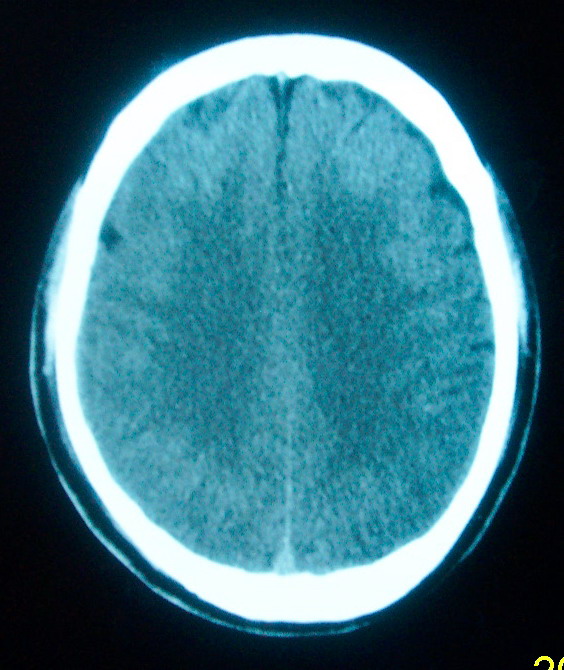

m     29    外伤1天   ct发现左额脑沟异常   请分析

未见明显异常,如果可疑巨脑回请做mri

我认为仅仅是左侧额叶脑回局部发育不良,脑沟与蛛网膜下腔略扩大而已没有巨脑回、硬膜下积液等情况。